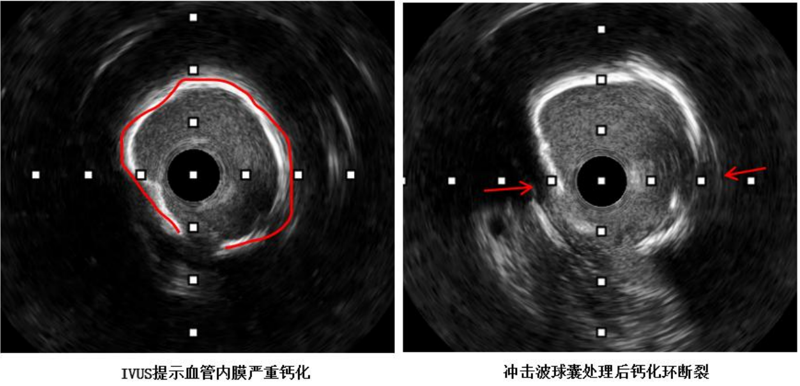

近日,中山大学附属第一医院(简称中山一院)广西医院心血管内科冠脉介入手术团队运用DEEPQUAKE-C冠脉血管内冲击波系统,顺利为一名冠脉严重钙化病变的冠心病患者开通堵塞的血管并完成支架植入,完成了DEEPQUAKE-C上市后全国首批、广西首例临床应用。68岁的杨阿姨(化名)近两年来反复出现胸痛症状,严重影响正常生活,得知捆绑调教 来了很多中山一院的派驻专家,为寻求进一步治疗,她来到捆绑调教 心血管内科住...